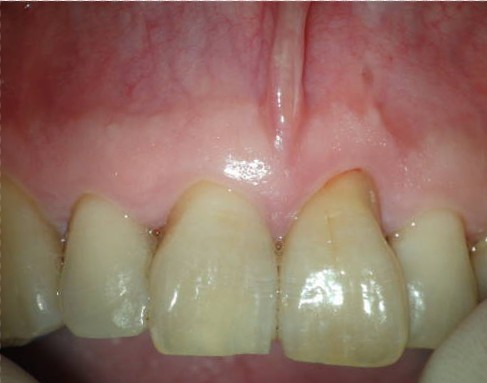

Después de realizarle un tratamiento de conductos  a la pieza 2.1 que presentaba una periodontitis apical crónica que fístulizaba, el paciente nos llegó los 4 meses con una nueva presencia de la fístula.

Con un aparente, buen tratamiento de conductos, estaría indicado una cirugía endodontica frente a este fracaso endodóntico por vía ortógrada, ya que necesitaríamos la ayuda de una obturación retrógrada.